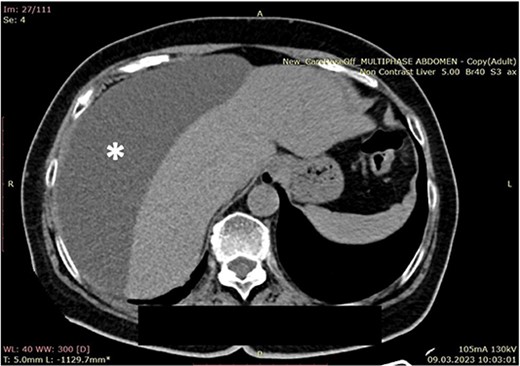

A 70-year-old female patient was transferred to our emergency department from another hospital with abdominal pain and vomiting in the past 2 weeks. The patient presented with clinical signs of acute abdomen. Physical examination showed diffuse abdominal tenderness. Abnormal laboratory findings comprehended Leucocyte count of 12.01 (3.5–10.0 × 109 g/L), Thrombocyte count of 456 (150.0–300.0 × 109 g/L), Neutrophil count of 9.7 (1.2–8.0 × 109 g/L), serum direct bilirubin value of 11.10 (0.0–8.6 mmol/L), and C-reactive protein value of 258 (0.0–5.0 mg/L). An abdominal computerized tomography (CT) scan revealed a large collection of fluid in the right hemiabdomen (Figs 1 and 2) and free gallstones in the abdominal cavity (Fig. 3).

Computerized abdominal tomography (axial scan) showing a large biloma in the right subphrenic region (asterisk).